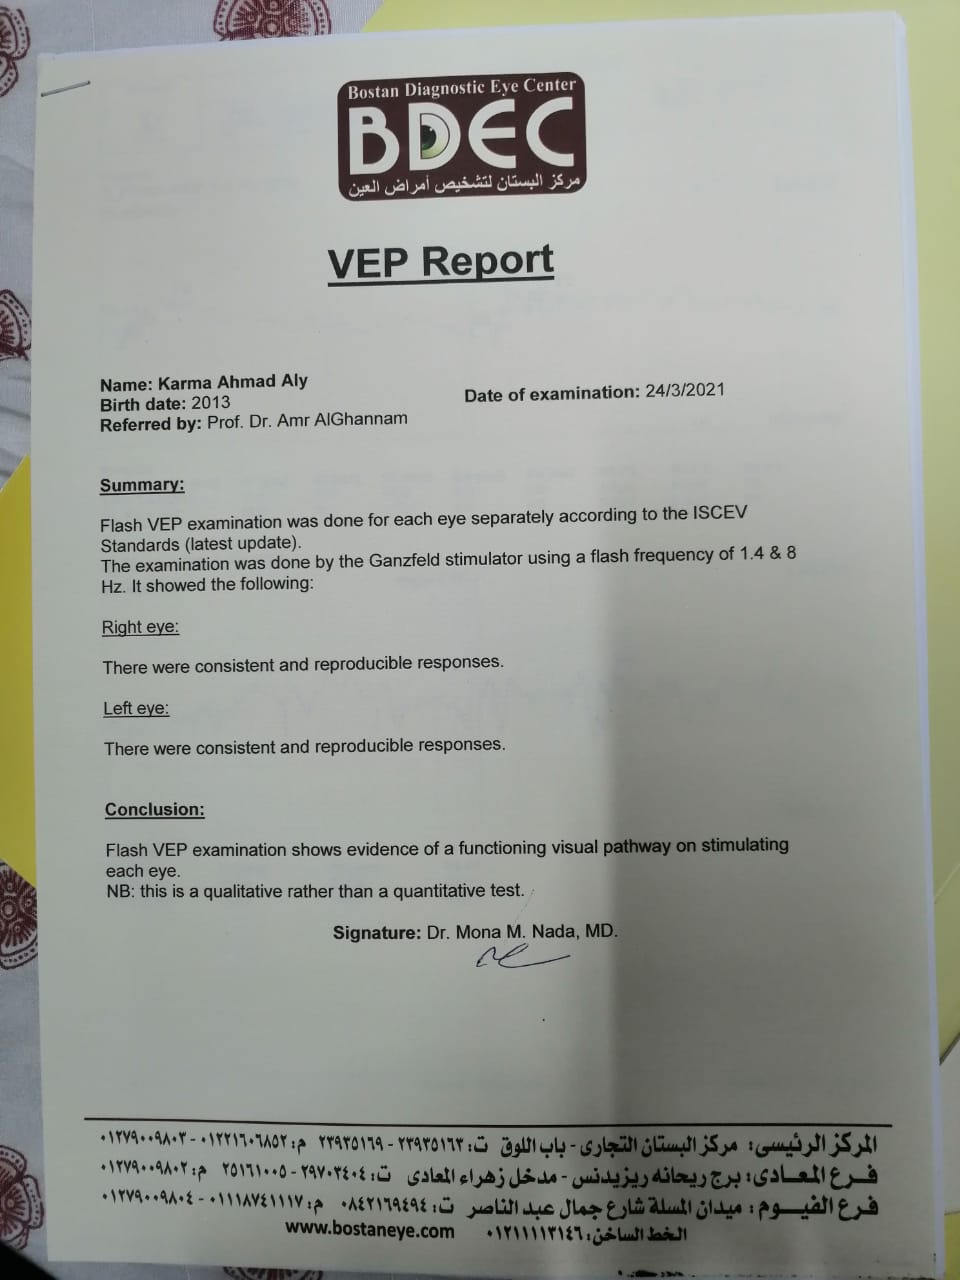

وأشار إلى أنه بعد خروج كارما من المستشفى تم إجراء فحوصات أخرى عليها، تبينت عدم التطابق بين التقارير الطبية لها بداخل المستشفى والفحوصات الجديدة.

وقال علي: "بنتي جالها ضمور في المخ وفي كل الحواس، بسبب الدوا الغلط، بنعملها علاج طبيعي بيتكلف في الشهر 20 ألف جنيه"، مشددًا": "هي بتفتح عينها بس".